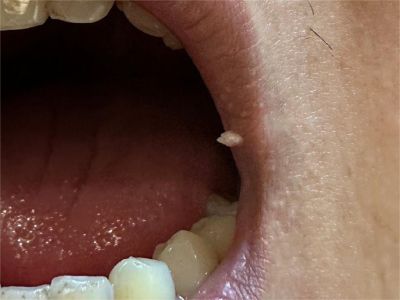

寻常疣症状图片

寻常疣可发生于身体的任何部位,但以手部为多,手外伤或水中浸泡是常见的诱发因素。典型皮损为黄豆大小或更大的灰褐色、棕色或皮色丘疹,表面粗糙,质地坚硬,可呈乳头瘤状增生。寻常疣发生在足底则为跖疣,因受压而形成淡黄或褐黄色胼胝样斑块或扁平丘疹,表面粗糙,界限清楚,边缘绕以稍高的角质环。发生在甲周者称甲周疣;发生在甲床者称甲下疣;疣体细长突起伴顶端角化者称丝状疣;发生于头皮及趾间的疣体表面常有参差不齐的突起称指状疣。